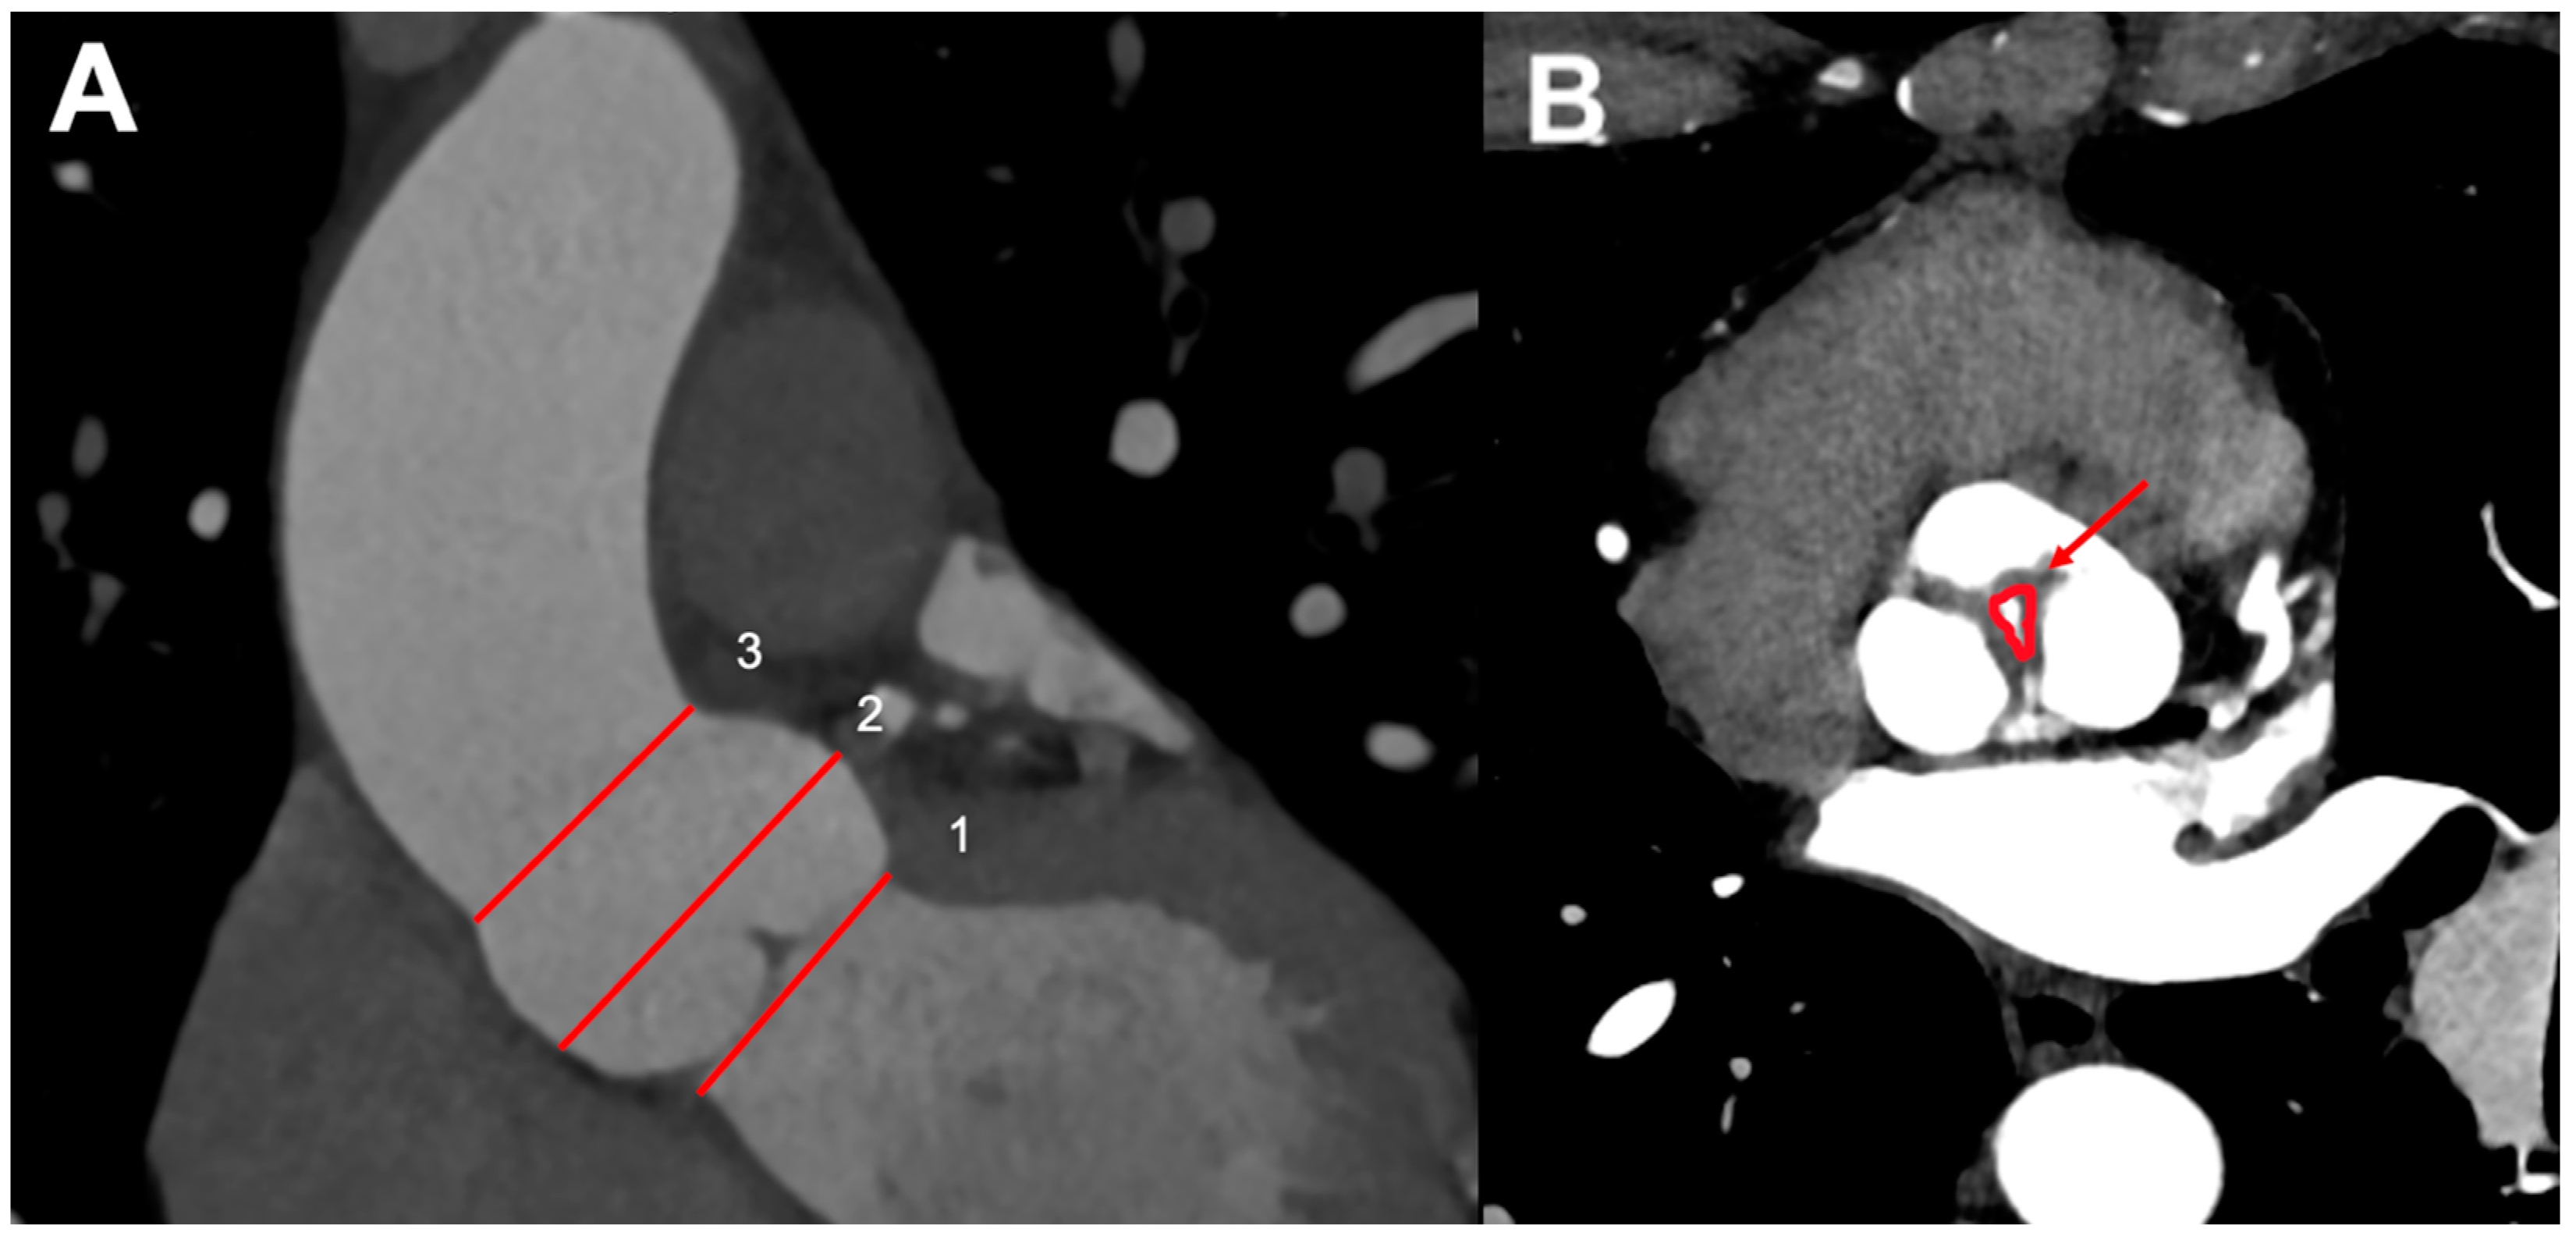

4.1. Aortic Root and Valve Evaluation